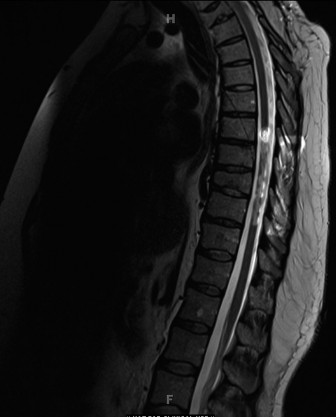

Magnetic Resonance Imaging Indications

An MRI of the entire neuroaxis (brainstem to sacrum) is an absolute requirement in the preoperative workup of congenital scoliosis. The incidence of intraspinal anomalies (such as tethered cord, syringomyelia, diastematomyelia, or Arnold-Chiari malformations) in congenital scoliosis approaches 20 to 40 percent.

In our index case, the MRI demonstrated a normal conus medullaris terminating at the L1 level, with no evidence of a thickened filum terminale or syrinx. The neural elements were normally situated within the canal, without any bony or fibrous septa splitting the cord. This negative finding is crucial, as any intraspinal anomaly must typically be addressed by neurosurgery prior to, or concurrent with, any major deformity correction to prevent catastrophic neurological injury during spinal manipulation.